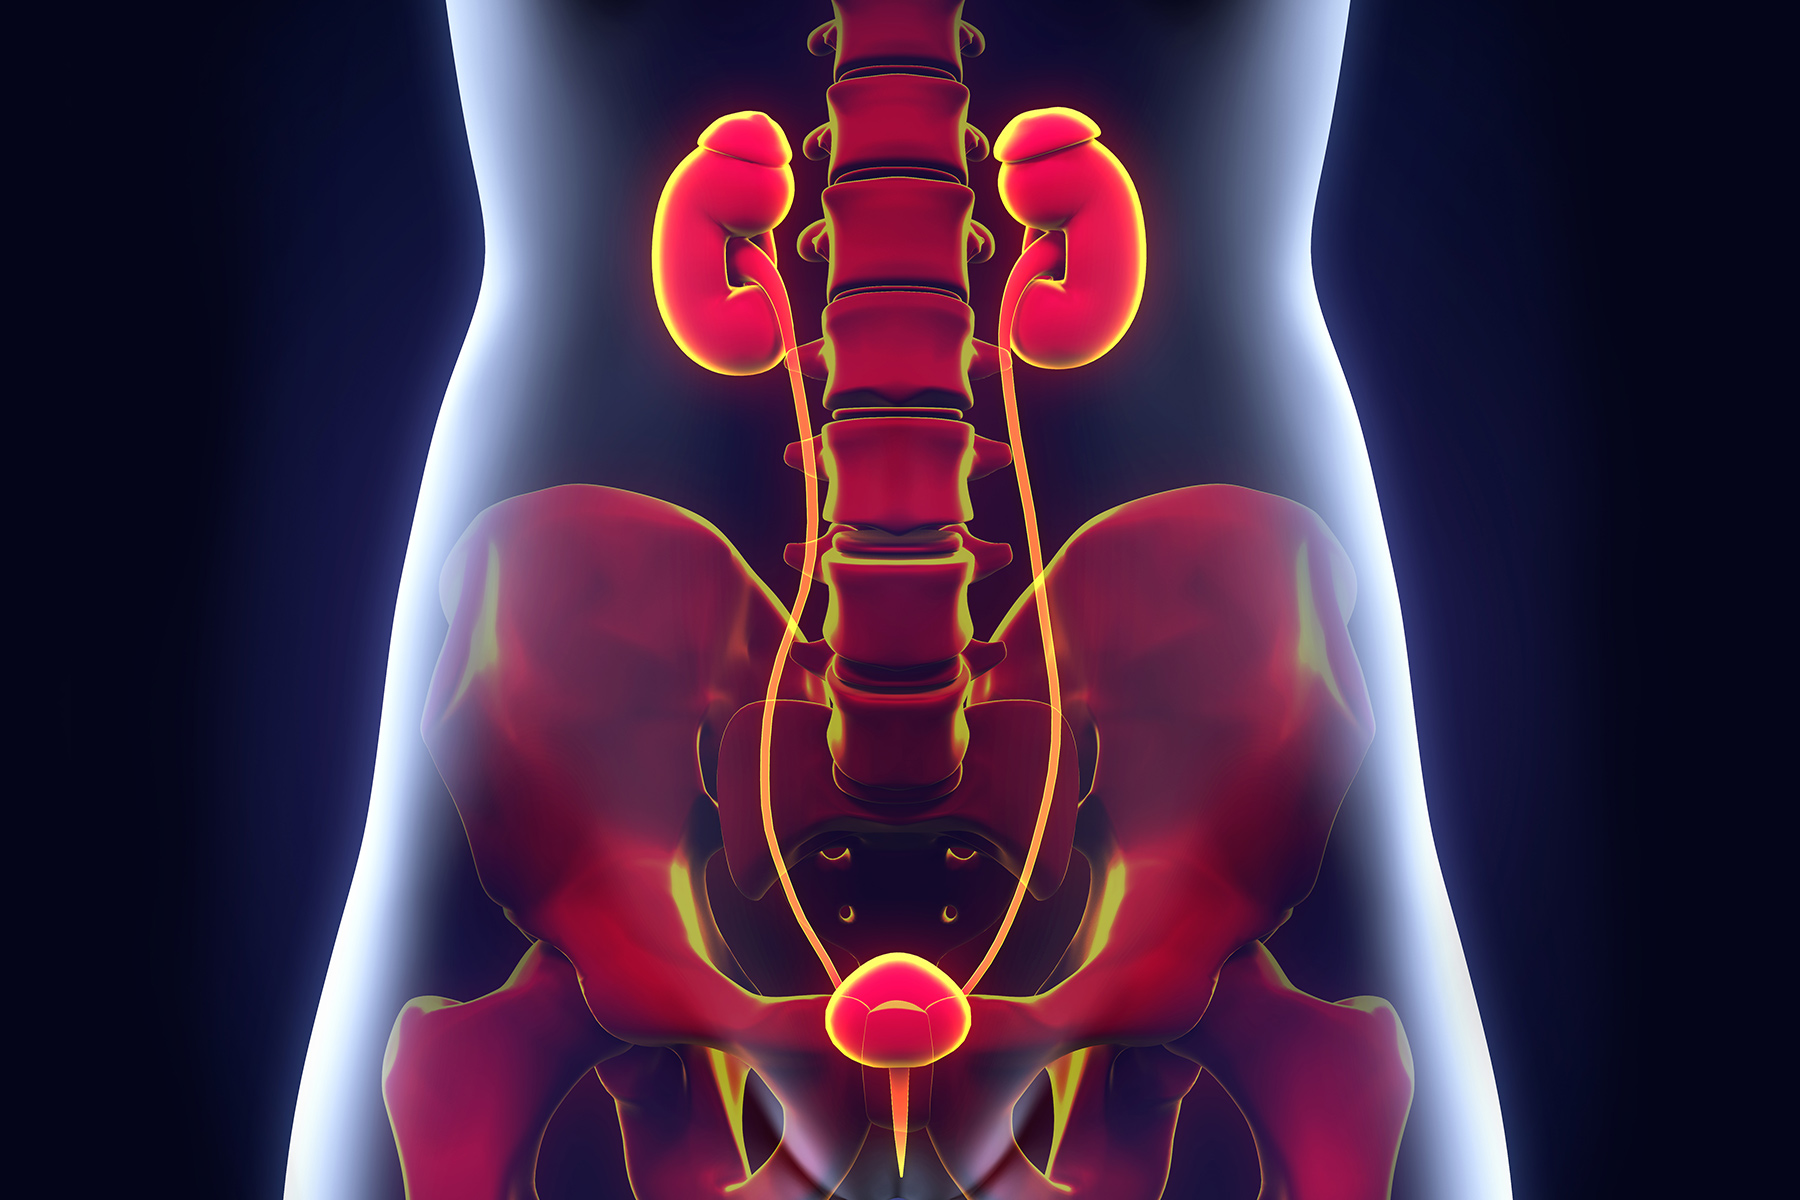

尿路感染

尿路感染是尿频的最常见原因。细菌感染肾脏,膀胱或将它们相互连接的管道。如果膀胱感染肿胀,无法容纳平时那么多的尿量。尿液可能会变得混浊,带血或有异味。尿路感染时,身体一侧或下腹部疼痛,还可能发烧,发冷,恶心和疼痛。医生一般会使用抗生素来治疗。